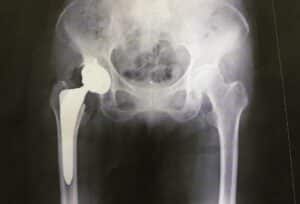

股関節 【葛飾区金町のやぎはし整体院】金町の「人工股関節全置換術(THA)」を回避する整体 金町で人工股関節全置換術の手術回避する整体とは?《やぎはし整体院が解説》 人は歩くとき片方の足に体重がかかると、その股関節に体重の3倍かかると言われております。 例えば50㎏の方の場合、股関節に150㎏の負荷がかかることになります。 言い換えれば、体重が1㎏増えるごとに股関節には、3㎏という大きな負荷が股関節にはかかっ...